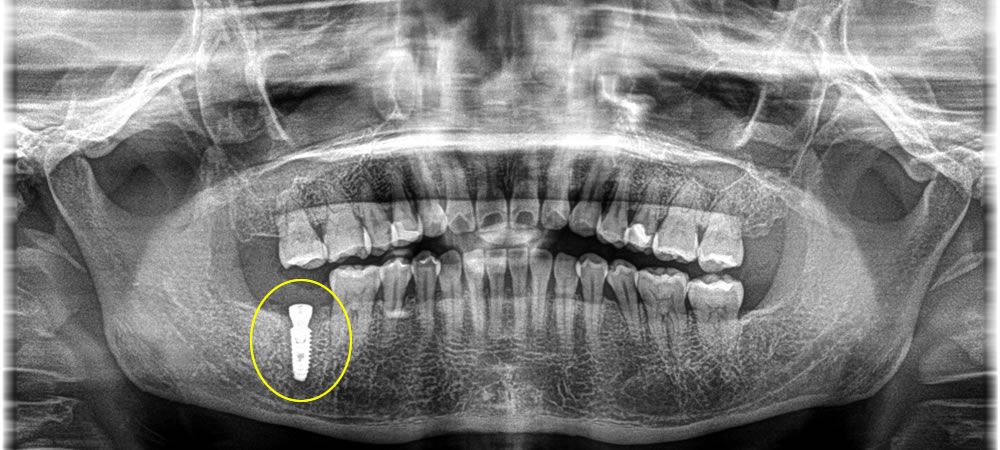

破折歯の抜歯・インプラント治療の実施

歯根が破折した歯をを抜歯し、計画通りの位置へインプラントを埋入しました。インプラントの持ちをなるべく良くするため、骨造成も同時に行っています。